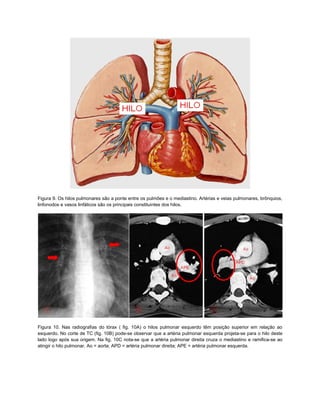

Figura 9. Os hilos pulmonares são a ponte entre os pulmões e o mediastino. Artérias e veias pulmonares, brônquios,

linfonodos e vasos linfáticos são os principais constituintes dos hilos.

Figura 10. Nas radiografias do tórax ( fig. 10A) o hilos pulmonar esquerdo têm posição superior em relação ao

esquerdo. No corte de TC (fig. 10B) pode-se observar que a artéria pulmonar esquerda projeta-se para o hilo deste

lado logo após sua origem. Na fig. 10C nota-se que a artéria pulmonar direita cruza o mediastino e ramifica-se ao

atingir o hilo pulmonar. Ao = aorta; APD = artéria pulmonar direita; APE = artéria pulmonar esquerda.